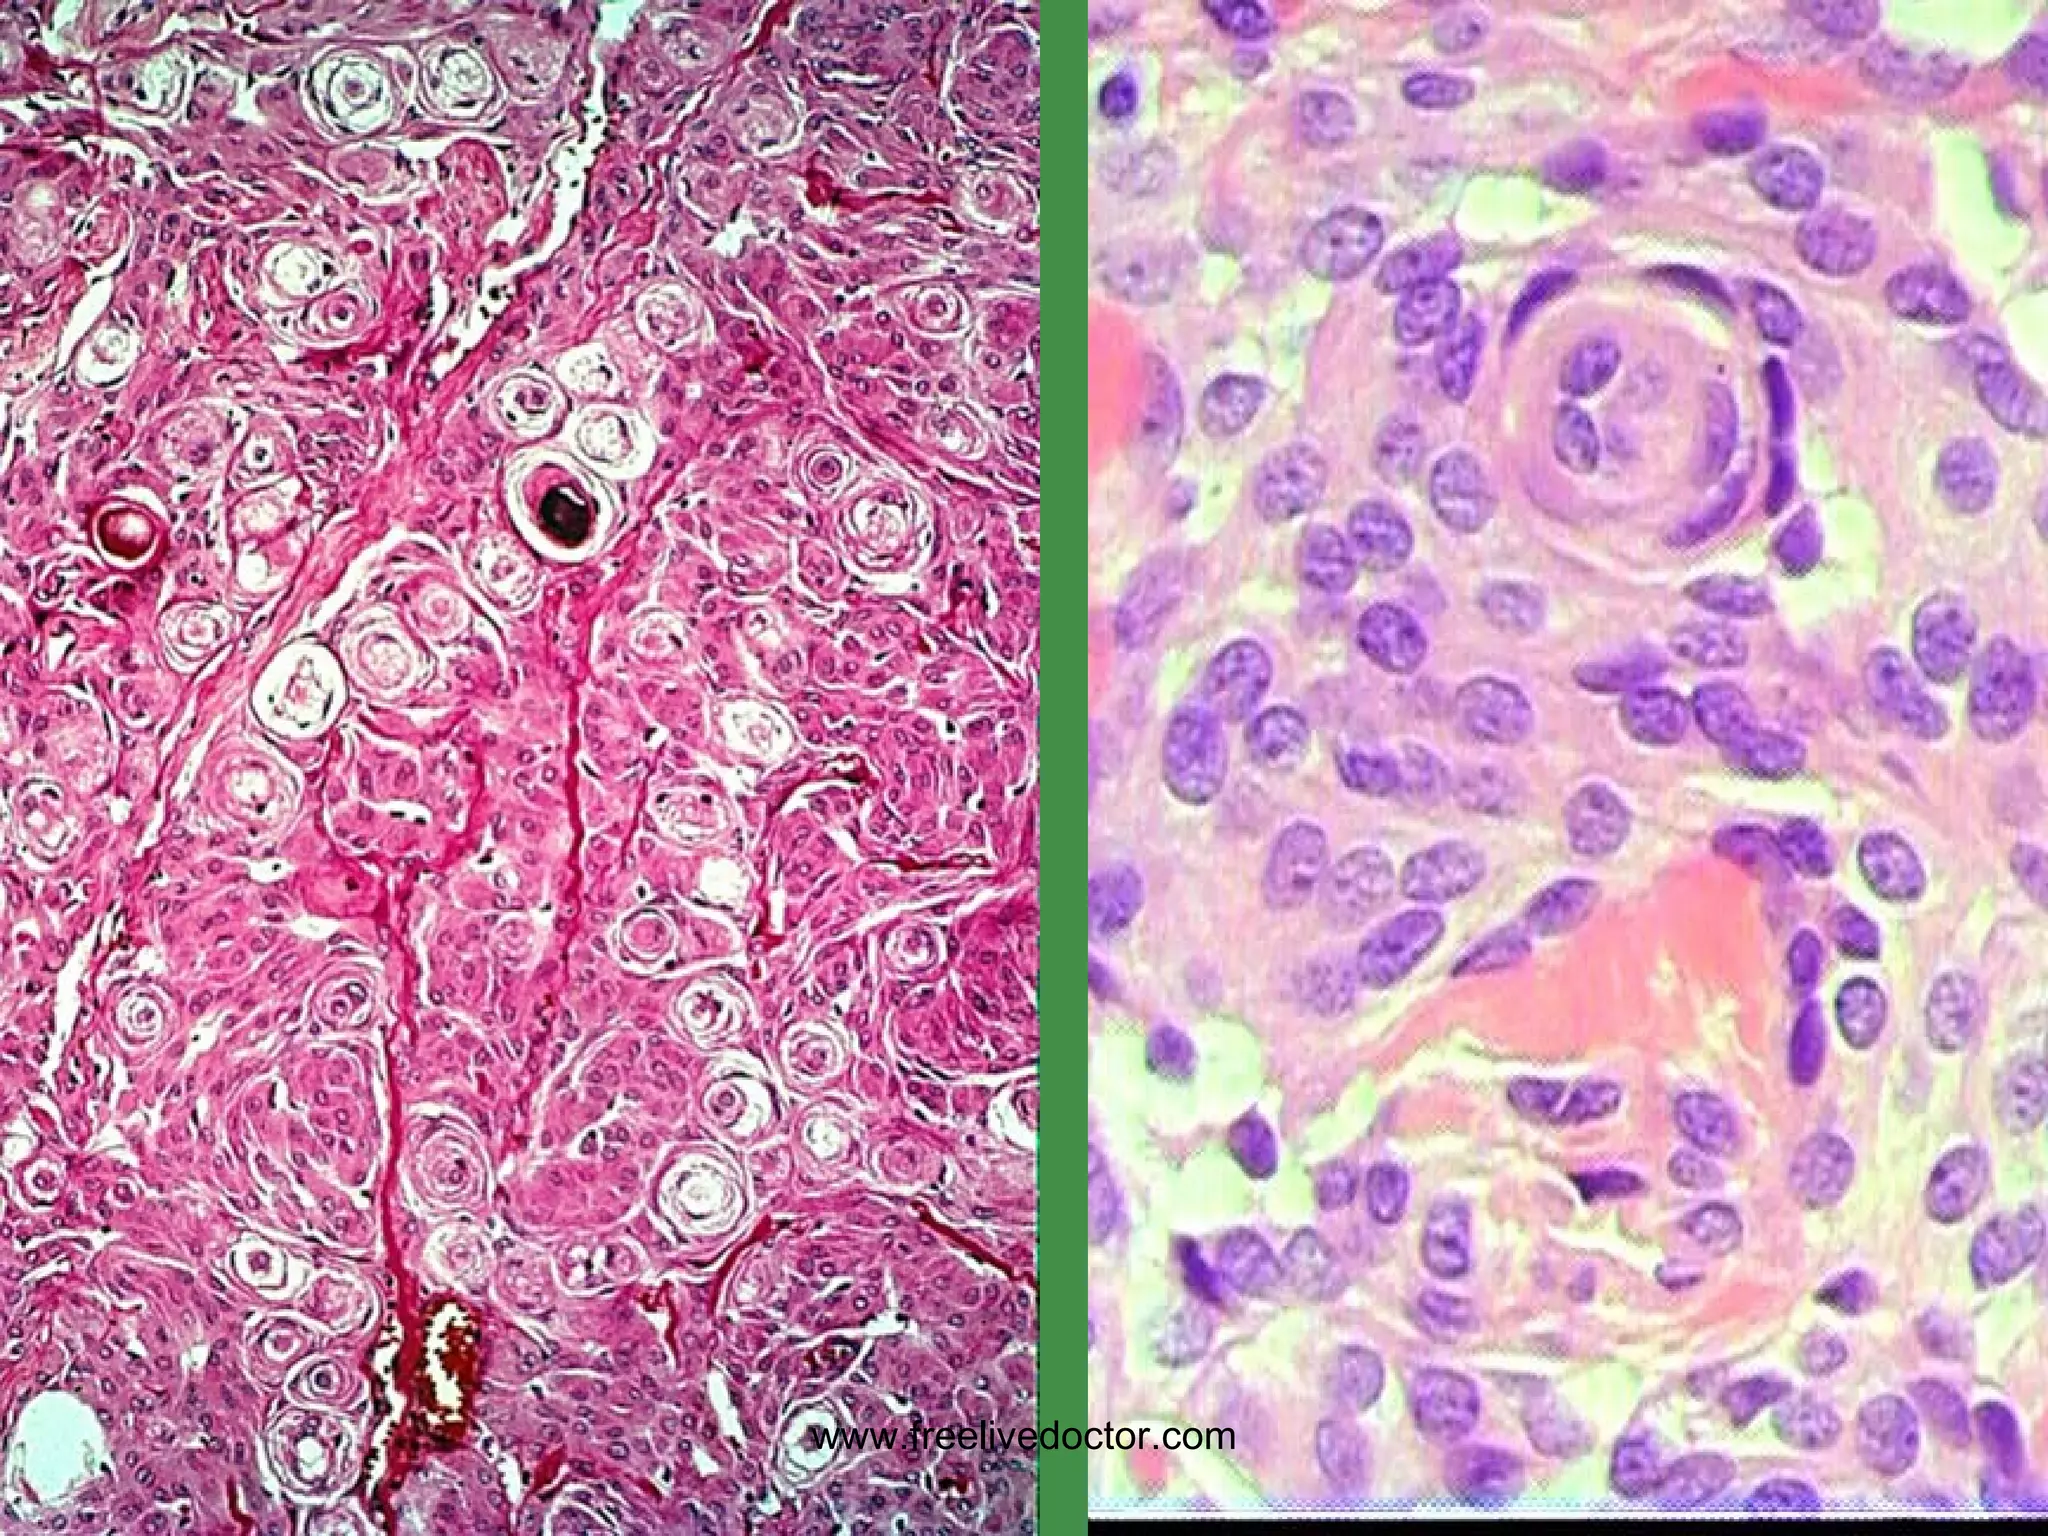

MENINGIOMAS Occur where dura is Very vascular BENIGN, but…. Can invade skull, etc. Only invade (displace) brain in areas adjacent to dura, i.e., parasagittal, falx, tentorium, venous sinuses Small, firm, and well defined like a SUPERBALL Often (usually?) have  PSAMMOMA   bodies www.freelivedoctor.com

• #164 Psammoma bodies are diagnostic of meningiomas in brain tumors! What other kinds of tumors have psammoma bodies? Ans: papillary carcinomas, classically in thyroid